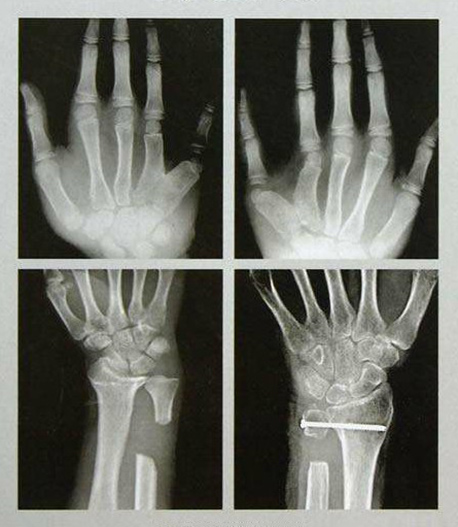

手足外科設(shè)有床位40張,舟山市醫(yī)學(xué)會(huì)手足外科專業(yè)委員會(huì)主任委員姜德欣主任醫(yī)師擔(dān)任學(xué)科帶頭人。科室提供上下肢和手足部的各種骨折、外傷、感染、畸形、功能障礙的手術(shù)治療,復(fù)雜創(chuàng)傷性四肢的保肢、斷指(趾)再植手術(shù),及各種軟組織缺損的修復(fù)、周圍神經(jīng)損傷、血管損傷的治療及糖尿病足等的綜合治療。